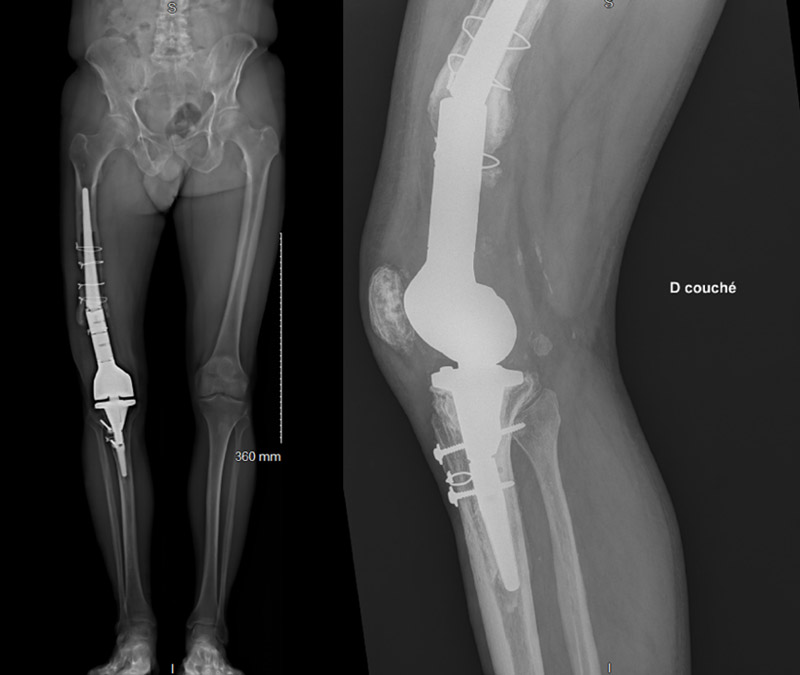

Management of a metaphyseal break of a custom-made massive knee prosthesis : imagery

• 69 y.o. male with pain, mainly at motion

• Walking only possible with crutches

• ext: -15 / flex: 70°

• No infection signs

• No skin suffering

• 2006: proximal right tibia fracture, osteosynthesis with plates and screws

• 2008: persistent knee pain, distal femur giant cell tumor diagnosis: removal of the osteosynthesis materials and massive reconstructive knee prosthesis

• 2019: knee prosthesis revision for aseptic loosening, new custom-made massive reconstructive knee prosthesis